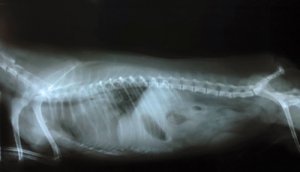

El diagnóstico diferencial para el síndrome de Wobbler se realiza por la observación de la columna y de las vértebras. Para ello, el veterinario solicitará la realización de una prueba de rayos X, una tomografía computadorizada, una resonancia magnética y una mielografía.